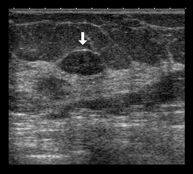

Ecografia mamària

És un mètode d'imatge on les ones sonores creen imatges dels vasos sanguinis, teixits i òrgans, incloent la mama. L'ecografia permet avaluar les anomalies visualitzades a la mamografia o a l'exploració clínica, diferenciant les lesions sòlides i les líquides (quists).

PAAF (punció) guiada per ecografia

En la punció aspiració amb agulla fina (PAAF) s'insereix una agulla fina guiada per ecografia fins a la zona sospitosa de la mama; a continuació s'aspira amb una xeringa, i s'obté escàs material cel·lular que s'envia per a l'estudi citològic. També s'utilitza per puncionar i evacuar quists mamaris i analitzar el seu contingut. És un procediment que dura molt pocs minuts i produeix lleugeres molèsties.